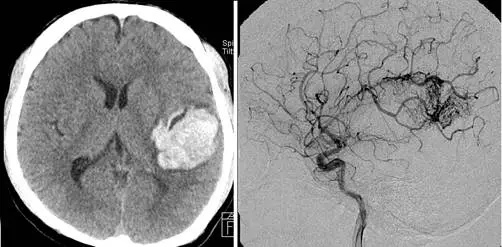

題目提供兩張圖像:

左圖(非對比頭部電腦斷層, non-contrast CT head): 可見右側顳頂葉(right temporal-parietal lobe)大面積高密度(白色)出血灶,出血呈葉狀分佈(lobar hemorrhage),位於大腦皮質下/淺表區域,周圍可見低密度水腫帶。出血部位不在基底核(basal ganglia)或丘腦(thalamus)等高血壓腦出血的典型好發位置,而是位於較淺表的葉狀位置,這提示血管結構異常(如 AVM)的可能性。

右圖(腦血管攝影, cerebral angiography): 可見腦實質內一糾結紊亂的異常血管團,呈現典型的「蚯蚓